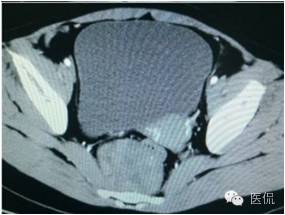

增强静脉期(CT值62HU)